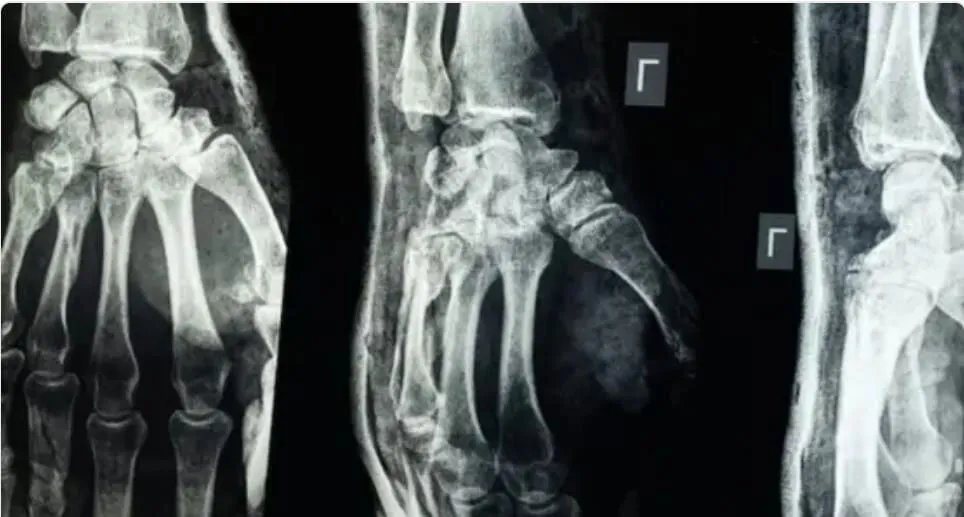

أعلن فريق بحثي في مقاطعة تشيجيانغ بشرق الصين عن تطوير "غراء عظمي" مبتكر، قادر على معالجة الكسور وتثبيت الشظايا العظمية في غضون ثلاث دقائق فقط. ووصف هذا الإنجاز بأنه اختراق علمي كبير في مجال جراحة العظام، وفقًا لما ذكره موقع "إن دي تي في" NDTV.

أكدت الاختبارات المعملية أن Bone-02 حقق نتائج جيدة من حيث السلامة والفعالية. وفي إحدى التجارب، أُجريت العملية في أقل من 180 ثانية (ثلاث دقائق)، بينما تتطلب طرق العلاج التقليدية وقتاً أطول لزرع صفائح فولاذية ومسامير.

أظهرت الاختبارات المعملية أن الغراء حقق قوة ربط تفوق 400 رطل، وقوة قص تبلغ نحو 0.5 ميغاباسكال، وقوة ضغط تقارب 10 ميغاباسكال. وأظهرت التجارب على أكثر من 150 مريضاً نتائج ناجحة، مما يعزز احتمالية أن يصبح بديلاً للزراعات المعدنية التقليدية المستخدمة في تثبيت العظام. ويشير العلماء أيضاً إلى أنه قد يقلل من مخاطر العدوى.